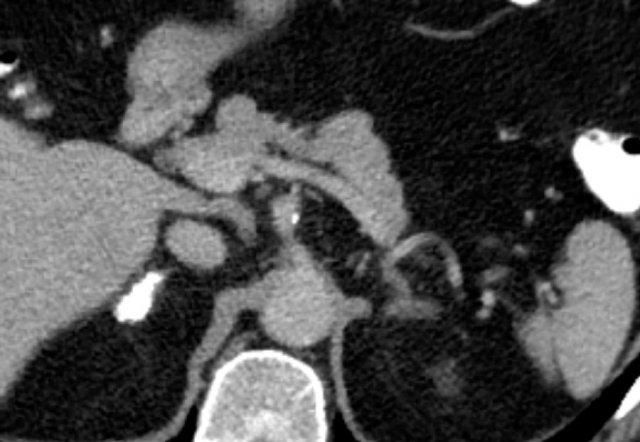

Các hình ảnh cho thấy u tình cờ tuyến thượng thận hai bên được phát hiện ở bệnh nhân 64 tuổi được chụp CT để phân tích phình động mạch chủ bụng.

Hình chụp pha động mạch cho thấy các tổn thương hai bên với tỷ trọng 50 HU.

Trên CT không tiêm thuốc thực hiện vài ngày sau, tỷ trọng ở cả hai tuyến thượng thận đều dưới 10 HU, xác nhận đây là các u tuyến giàu lipid.